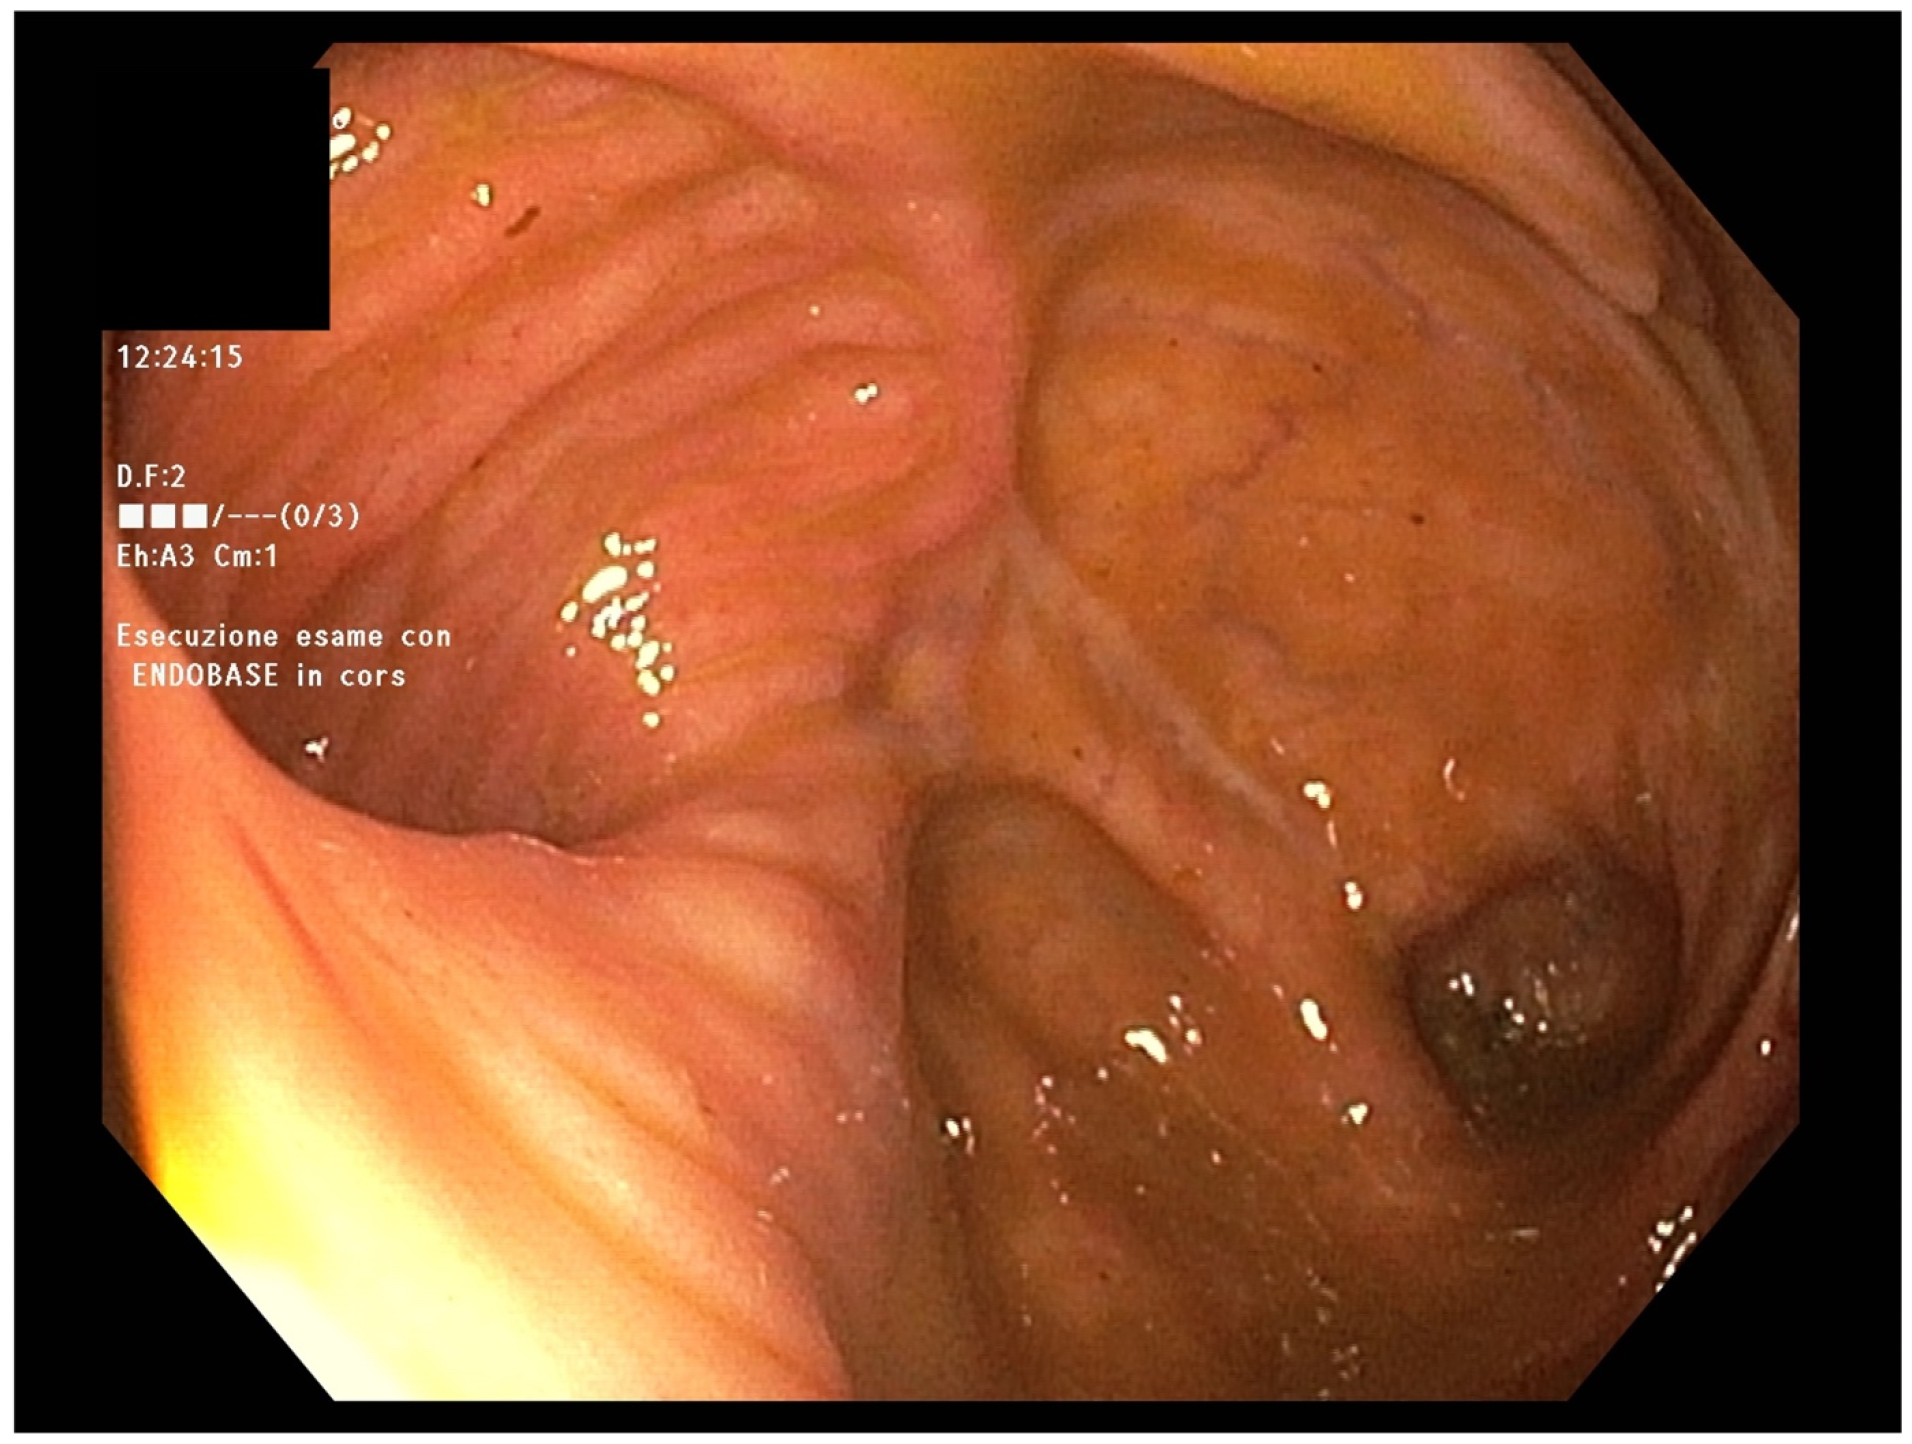

In January 2022, the patient complained of worsening abdominal pain localized in the right low quadrant, so ileo-colonoscopy and MRE were performed again, confirming stenosis of the terminal ileum and ascending colon (Figure 2).

Figure 2. Suspected stenosing Crohn’s disease at MRE (arrow).